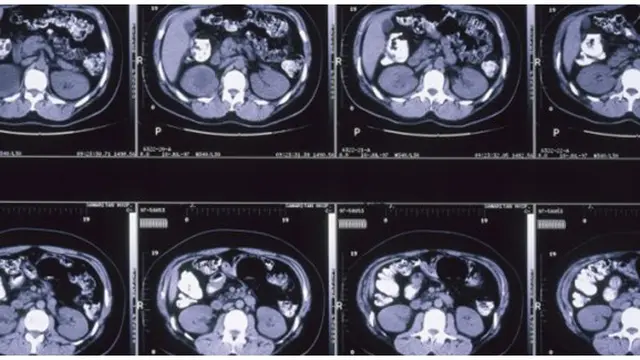

Pembunuh selamat karena scan otak

John McCluskey bukanlah orang yang menyenangkan. Pria ini pernah melarikan diri dari penjara Arizona, membunuh suami istri yang sudah tua, membakar tubuh mereka, dan mencuri harta bendanya. Akhirnya McCluskey tertangkap kembali dan dinyatakan bersalah atas apa yang dilakukannya. Namun tim pembela McCluskey menunjukkan bukti yang mengubah hukuman pria mengerikan ini. Hasil dari scan otak yang dilakukan pada otak McCluskey menunjukkan 10 area otak tidak aktif namun 17 area lainnya bekerja keras.

Misalnya amigdala, bagian ini tidak bisa menafsirkan sinyal bahaya dengan benar dan sering kali dikirim sebagai "false alarm" ke seluruh otak, hal ini menyebabkan dia bertindak impulsif. Bahkan lobus frontalnya cacat dan rusak. Kemudian pembunuhan yang dilakukan McCluskey diklaim sebagai tindakan yang sebenarnya tidak direncanakan, melainkan akibat gangguan biologis yang terjadi pada otaknya. Meskipun McCluskey selamat dari hukuman mati, namun hakim memutuskan untuk menjatuhkan hukuman seumur hidup tanpa pembebasan bersyarat. Mungkin ngeri juga ya Ladies jika harus melepaskan pembunuh seperti McCluskey.